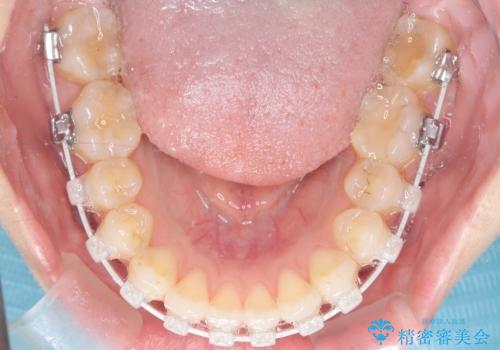

今回の矯正では、装置が目立たないよう透明なブラケットと白いワイヤーを使用。さらに、効率的な歯の移動のために、歯の裏側にリンガルアーチを設置しました。また、確実な奥歯の移動のために**TAD(矯正用アンカースクリュー)**を一時的に使用。これにより、犬歯を狙った位置へ正確に動かすことが可能に。目立ちにくい装置で快適に過ごしながら、理想的な歯並びと咬み合わせを獲得していただけました。